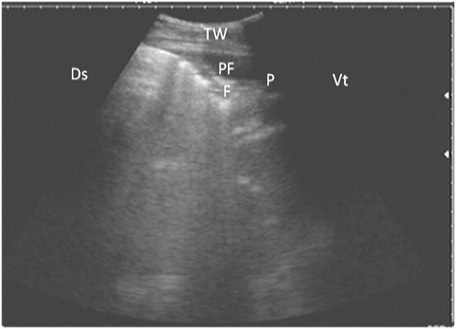

Ultrasonography of the lung of a diseased cow using a 3.5 MHz transducer. The image shows hypoechoic fluid in the pleural cavity with echogenic bands that were hyperechoic with comet-tail artifacts. Pleura (P), fibrin (F), pleural effusion (PE), and the thoracic wall (TW). The right part of the image is ventral (Vt) and the left is dorsal (Ds).